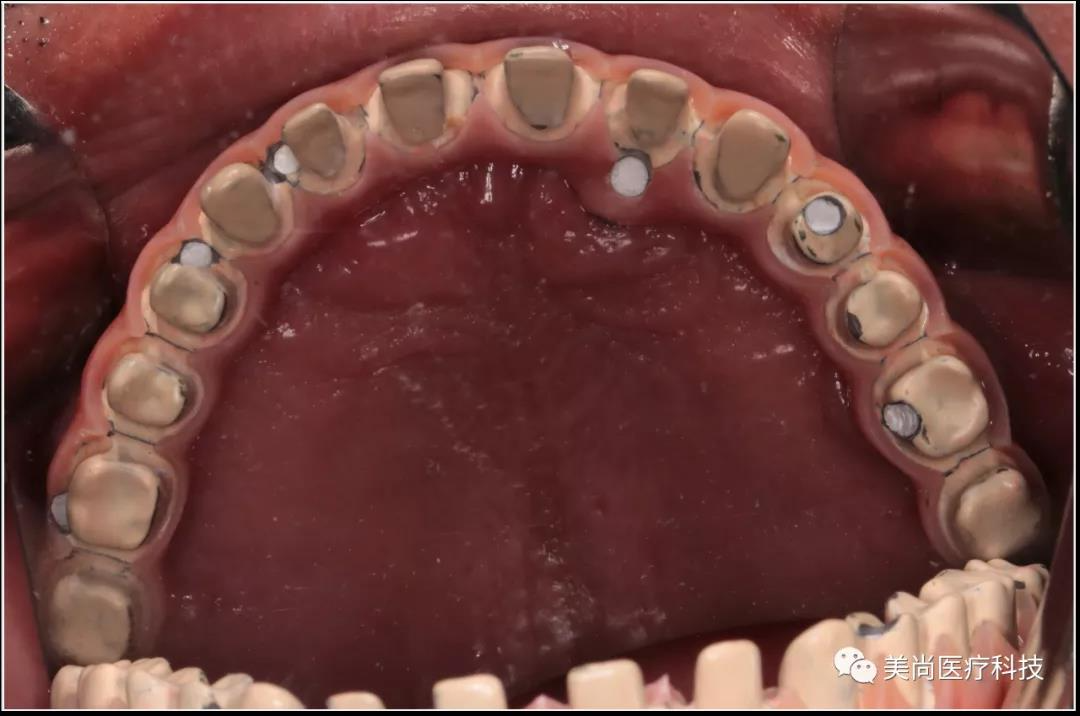

口内检查情况

▲口内余留21,22,23,42,43,44,其余牙齿缺失,牙齿缺失区牙槽嵴明显萎缩

▲口腔卫生环境差,余牙II度~III度松动

制作种植导板